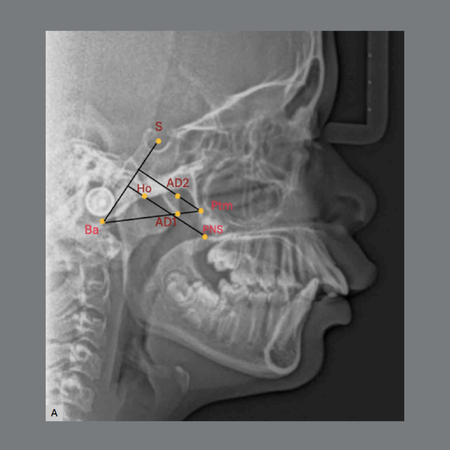

Leia maisIntroduction: Nasopharyngeal obstruction may influence craniofacial growth, lead to psychosocial impairments, and adversely affect quality of life. Thus, it is important to identify the potential of orthodontic therapies to alter the dimensions of the airways. Objectives: To evaluate the long-term changes in pharyngeal airway dimensions in skeletal Class II patients treated with cervical headgear appliance. Material and Methods: A retrospective study was conducted with 20 patients treated by...